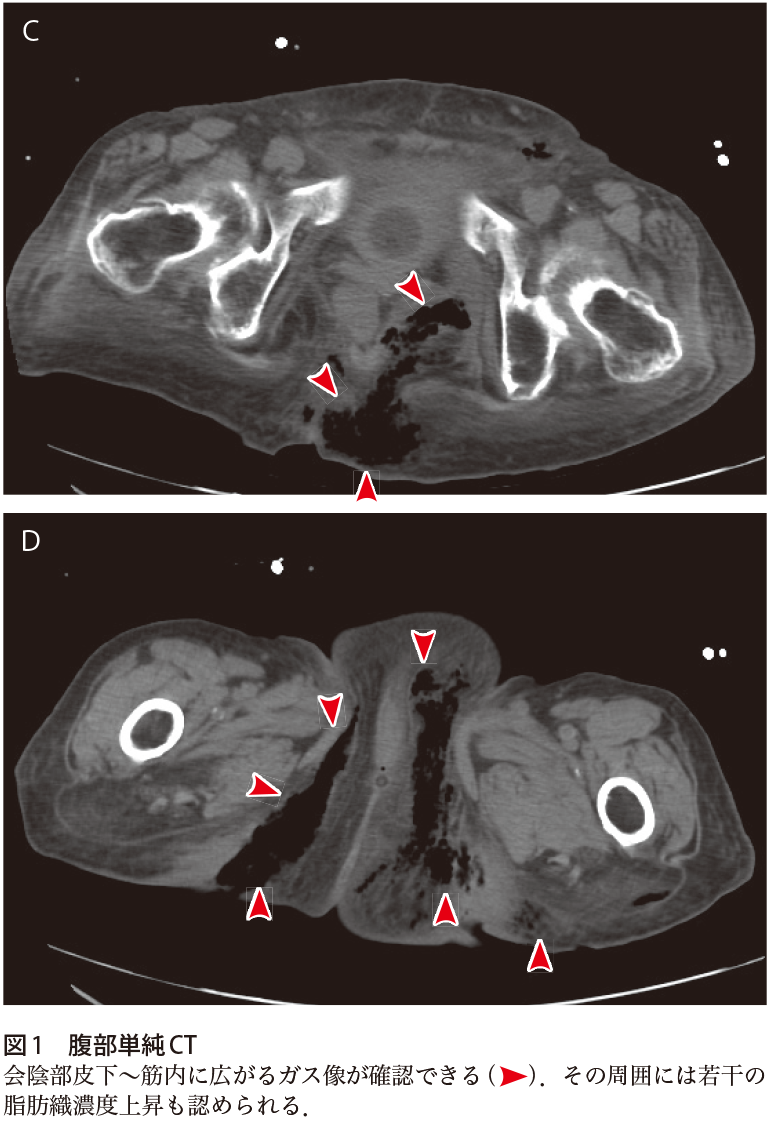

· 壊疽 画像 壊疽 画像画像所見図1に提示した単純ctで,左陰嚢から 陰茎部に皮下気腫を認めた(矢印)。 フルニエ壊疽 と判断し,緊急でドレナージ及びデブリードマンを 依頼した。 手術所見図2に手術所見を示す。 左陰嚢の発赤と 腫脹を認めする性器の壊死をフルニエ壊疽と報告し4),現在では 陰部や肛門周囲から発生した壊死性筋膜炎をフルニエ 壊疽と呼んでいる.今回,我々はフルニエ壊疽の1例 を経験したので報告する. 症例 42歳女性,基礎疾患に未治療の糖尿病あり,1週間フルニエ壊疽の診断・治療に関する研究 のお知らせ 研究に関するお知らせ 帝京 大学 医学部附属 病院では以下の研究を行います。 本 研究は 、倫理委員会の審査を受け承認された後に、関連の研究倫理指針に従って実施されるものです。 研究期間

和田 武 画像診断 Ivr医 フルニエ壊疽の画像診断まとめ フルニエ壊疽 会陰部に生じる壊死性筋膜炎 は急速進行する疾患であり 迅速な診断と正確な進展範囲の把握が求められます 会陰部軟部組織の腫大や脂肪織混濁像 皮下や筋間のガス像 Ctで90